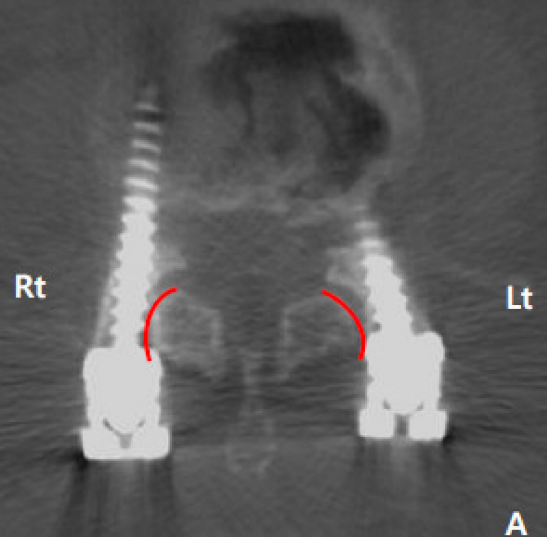

4.Seo分级

0级:螺钉明显避开关节

1级:螺钉接触或疑似已侵入关节

2级:螺钉明显破坏关节

左侧1级,右侧2级